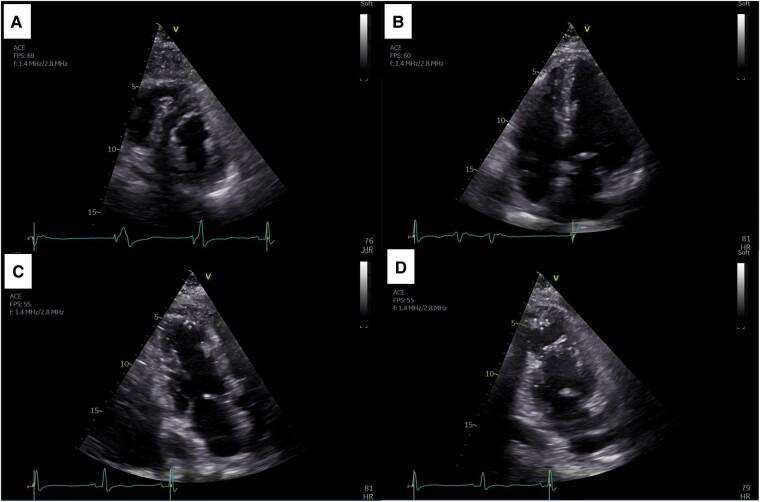

CASE SUMMARY

We describe a TTS case presented with cardiogenic shock due to ventricular septal rupture (VSR). Successful treatment involved mechanical circulatory support followed by VSR surgical closure.

我们描述了一例因室间隔破裂(VSR)导致心源性休克的TTS病例。成功的治疗包括机械循环支持,随后进行VSR手术闭合。